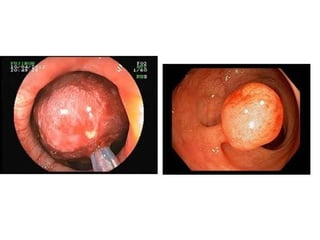

Non Invasive Polyp

Large polyps may contain cancer that is completely contained within the polyp.

In these cases, polypectomy is considered curative, provided:

- The cancer is completely contained within the resected tissue

- No lymphovascular invasion

- Resection margins are free of cancer

Invasive polyps features that suggest the presence of malignancy include:

- Friability

- Induration

- Ulceration

- Smooth velvety surface (e.g. non-granular laterally spreading tumor in the Rt colon)

- Non lifting sign

Invasive Polyp